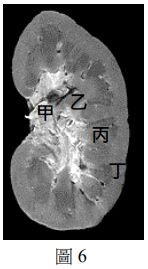

30. 某生想製備組織切片,以利用顯微鏡觀察腎小體的構造。圖6為豬腎臟縱切剖面,該生應該取哪一部分的薄片來製作玻片標本? (A) 甲 (B) 乙 (C) 丙 (D) 丁